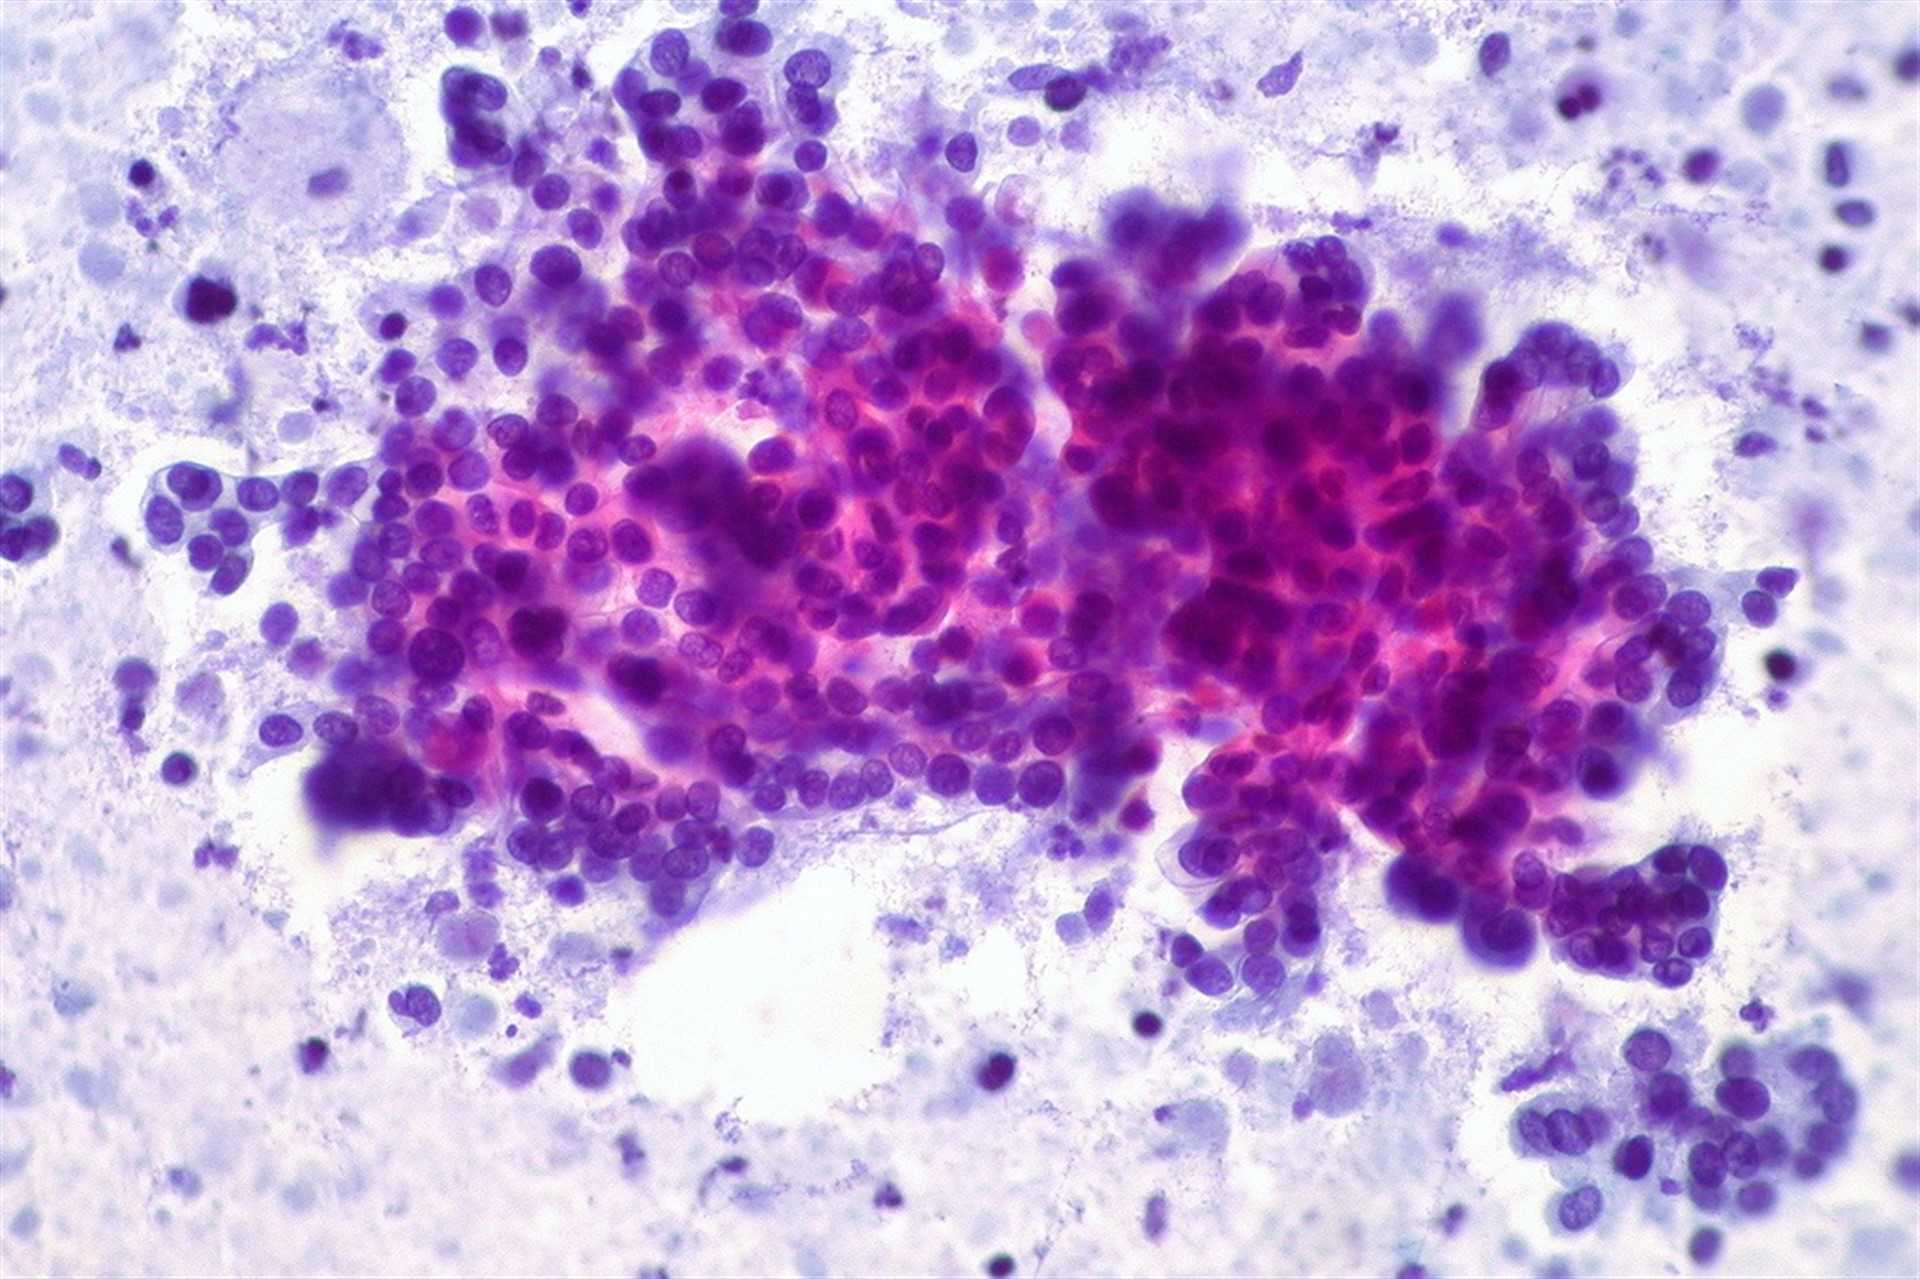

VALÈNCIA. (EP). Más de 7.000 personas desarrollan un cáncer de páncreas cada año en España, con una mortalidad estimada para 2018 de 7.279 fallecimientos. Así, es el noveno tumor en frecuencia en España y, sin embargo, debido a su alta letalidad, supone la tercera causa de muerte por cáncer, según detalla la Sociedad Española de Oncología Médica (SEOM) dentro de su campaña de comunicación 'En Oncología cada avance se escribe con Mayúsculas'.

"En los últimos años se ha observado un incremento en la incidencia de esta enfermedad, posiblemente debido al envejecimiento poblacional, al aumento en la prevalencia de obesidad y a otros factores aún desconocidos. El cáncer de páncreas ha sido una neoplasia genéticamente muy compleja y heterogénea, resistente de forma inherente a la mayor parte de las terapias convencionales. Sin embargo, en los últimos años se están logrando importantes avances en todos los estadios de la enfermedad", explican desde SEOM.

Uno de los aspectos "más importantes" ha sido el avance en la caracterización molecular del cáncer de páncreas. "La identificación de los genes más frecuentemente mutados (KRAS, CDKN2A, TP53 y SMAD4), la identificación de dianas moleculares potenciales como las traslocaciones de ALK, presentes hasta en un 1,3 por ciento de los pacientes menores de 50 años, así como el reconocimiento del impacto de las mutaciones BRCA1/2 o la expresión de hENT1, que podría predecir la respuesta a gemcitabina al menos en el contexto adyuvante, han sido cruciales para una mejor comprensión de la enfermedad", detallan.